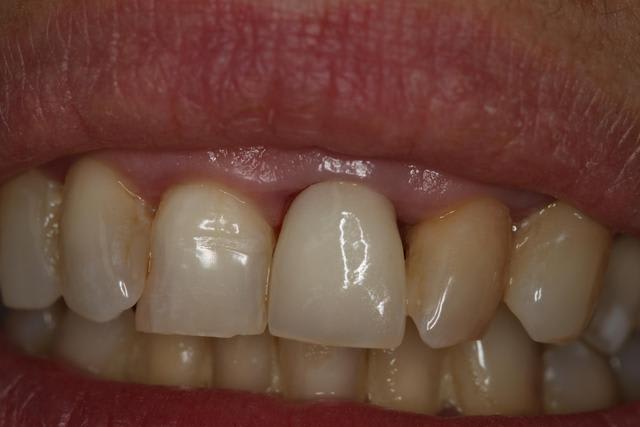

Jour d'essayage : le prothésiste m'a fait les 2 possibilités Emax et Zircone :)

Emax = trop translucide / parait trop gris encore. Teinte correspondant pourtant. Souci de grade d'opacité ?

Zircone mieux : je pense par contre que c'est bien l'armature zircone qui fait toute l'opacité.

Pas assez "jaune" au collet, et manque de translucidité sur les bords proximaux.